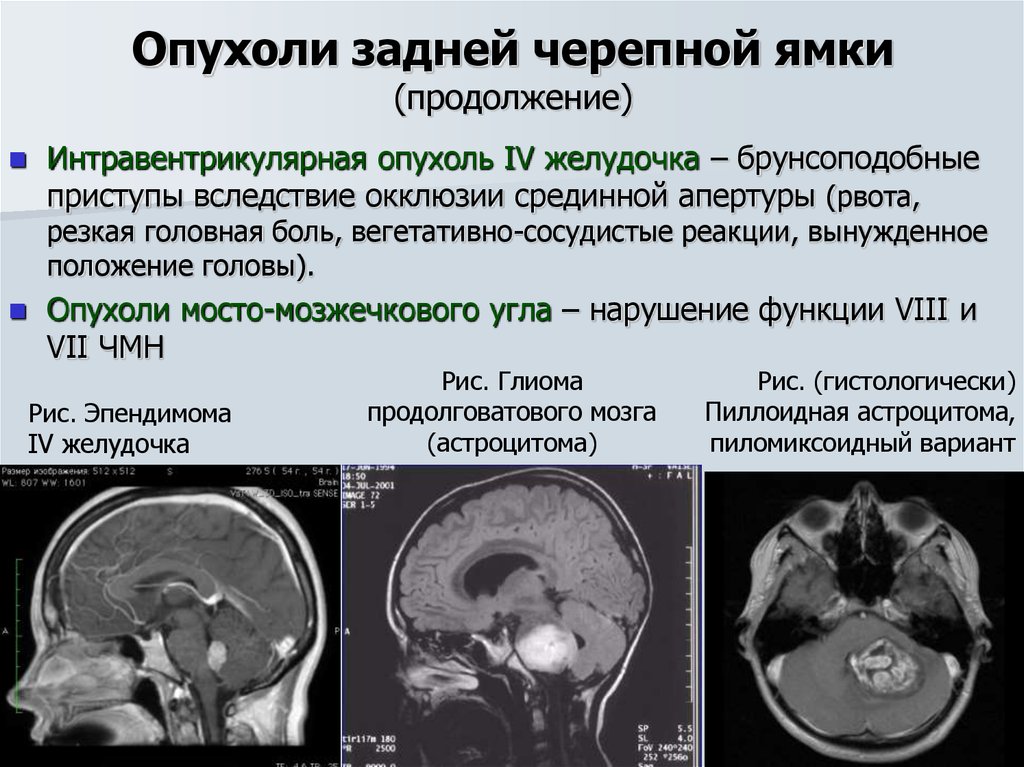

Кт при опухоли надпочечников. Кортикостерома надпочечника кт. МСКТ объемное образование надпочечника. Кт мрт аденома надпочечника. Опухоли задней черепной ямки. Объемное образование задней черепной ямки. Опухоли задней черепной ямки клиника.

Опухоли задней черепной ямки. Объемное образование задней черепной ямки. Опухоли задней черепной ямки клиника. Канцер молочной железы. Онкология грудной железы. Онкологические заболевания груди. Опухоль молочной железы.